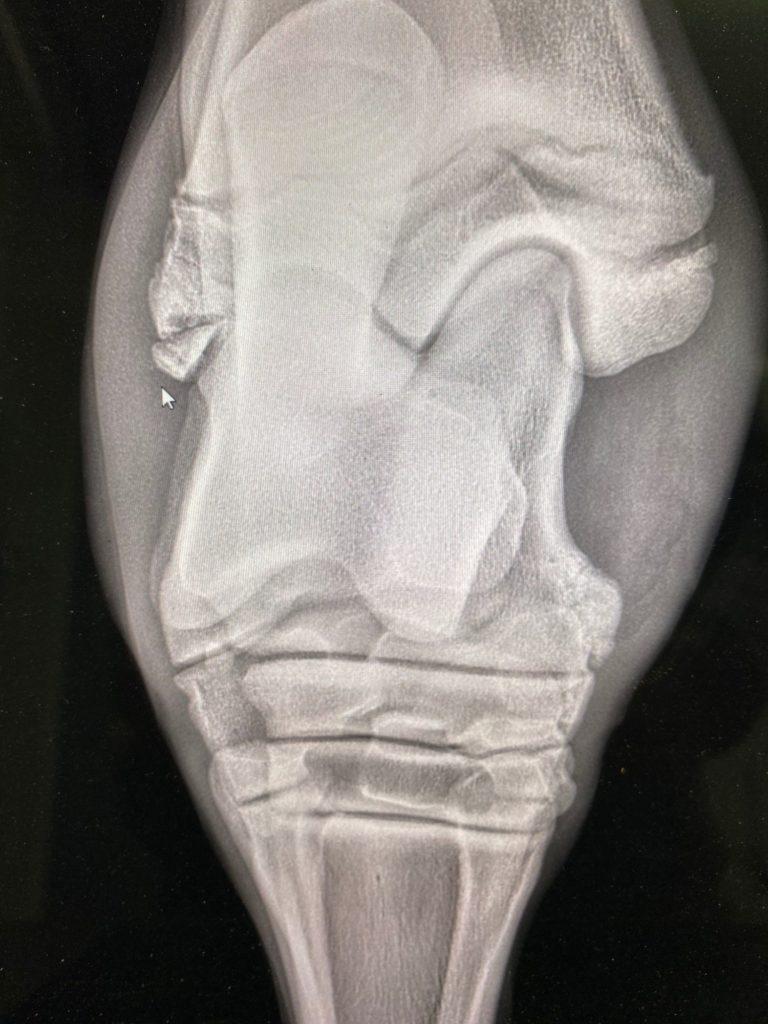

Etter en klinisk undersøkelse kom man frem til at det var på sin plass å ta røntgenbilder av leddet.

Det viste seg raskt hvorfor hasen var så hoven! Cortino hadde slått løs en bit av tibia (leggbeinet), helt nederst inn mot haseleddet. Denne biten lå og skapte irritasjon i leddoverflaten, og kunne på sikt medføre at han fikk problemer med foten som hadde gjort at han ikke var i stand til å fungere som ridehest.